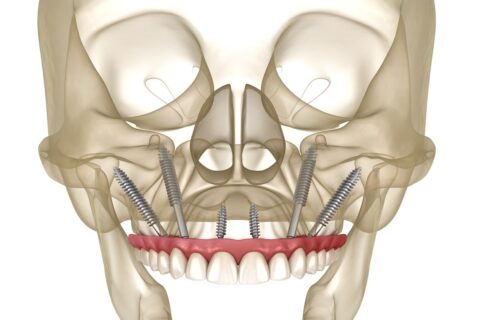

Zygomatic implants, also known as Zygoma implants, are an alternative to bone grafting techniques for the upper jaw and offer a viable option for individuals who desire dental implants but are severely deficient in upper jaw bone. These implants are inserted into the zygomatic bone (cheekbone) to support dentures, bridges, and upper jaw (maxillary) teeth, in contrast to traditional “root form” dental implants that are implanted into the jaws to replace teeth.

They pass transversely through the weak area of the upper jaw and attach to the bottom of the cheekbones via your sinuses.